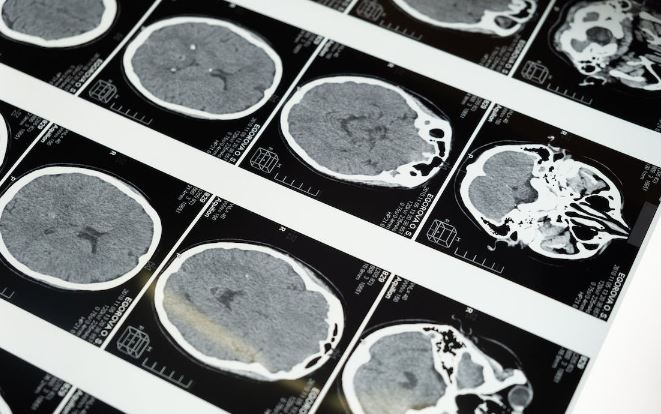

Menenjit varlığını belirlemek için birkaç kan testi yapılabilir. Tam kan sayımı ve toplam protein seviyesi iki yaygın testtir. Bir prokalsitonin kan testi, başka bir yararlı testtir. Bu kan testleri genellikle spinal musluk ile aynı anda yapılır ve hastanın kanındaki protein, antikor ve hücre düzeylerini karşılaştırabilir. Çeşitli görüntüleme testleri, omurilik ve beyindeki iltihabın derecesini gösterebilen bir bilgisayarlı tomografi taraması da dahil olmak üzere menenjit tanısını doğrulayabilir.

Menenjit tedavisinde ilk adım hızlı bir teşhistir. Hastalık hızlı bir şekilde tespit edilirse, enfeksiyonu tedavi etmek ve ilerlemesini önlemek için antibiyotik verilebilir. Teşhis testleri arasında spinal musluğu (lomber ponksiyon da denir) ve kan kültürleri bulunur. Başın BT taraması da menenjitin nedenini belirlemede yararlıdır. Beyindeki ve omurilikteki (beyin omurilik sıvısı) sıvıyı kontrol etmek için bir lomber ponksiyon kullanılır. Ayrıca beyin omurilik sıvısında bakteri, anormal glikoz konsantrasyonları veya enflamatuar hücrelerin bulunup bulunmadığını da belirler.